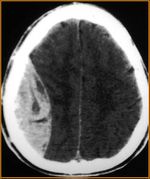

- Extra-axial

- Epidural hemorrhage

- Subdural hemorrhage